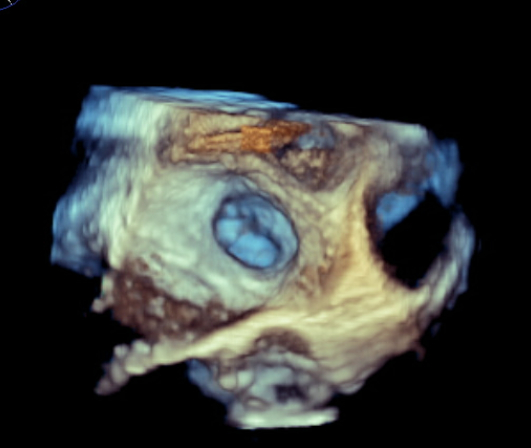

82-year-old male who presented with symptoms of progressively worsening shortness of breath and palpitations for 4 days. He was recently diagnosed with non-small cell carcinoma and underwent a left upper lobectomy a few months prior. Upon arrival, patient was tachycardic, with a heart rate in the 140s, requiring 5-6 L nasal cannula to maintain oxygen saturation above 92%. EKG revealed new onset atrial fibrillation with rapid ventricular response. Laboratory testing was remarkable for elevated NT-pro BNP to 4,000. CXR revealed bilateral pulmonary congestion consistent with pulmonary edema. Transthoracic echocardiogram was significant for severely reduced EF to 15-20%, previously normal. The patient was admitted for management of new onset-atrial fibrillation & HFrEF likely due to tachycardia-mediated cardiomyopathy. Cardioversion was initially planned; however transesophageal echocardiogram revealed an unexpected thrombus at the os of the left superior pulmonary vein. No thrombus was seen in the left atrial appendage. The patient was started on IV digoxin and low-dose esmolol drip for rate control along with a heparin drip for anticoagulation. However, the patient had sinus pauses for up to 5 seconds on esmolol drip. Given the limitation to control the heart rate, the patient underwent placement of CRT-P device. He was medically optimized and discharged with plan for outpatient cardioversion vs Atrial fibrillation ablation.

Atrial fibrillation with rapid ventricular response is a common precipitant of heart failure, often requiring rhythm control. The presence of intracardiac thrombus is a well-established contraindication due to the risk of systemic embolization. While most thrombi form in the left atrial appendage, our patient was found to have a thrombus in the left superior pulmonary vein, a unique and exceedingly rare finding. Most cases of pulmonary vein thrombosis are seen after catheter ablation, lobectomy, Lung transplantation, etc. Our case presented a unique dilemma due to the lack of guidelines addressing thromboembolic risk and cardioversion in this context. Therefore, a conservative approach was chosen with rate control and systemic anticoagulation. This case also highlights the value of comprehensive imaging like transesophageal echocardiography for through evaluation of pulmonary vein ostia in addition to left atrial appendage thrombus, especially in the context of recent thoracic surgery.